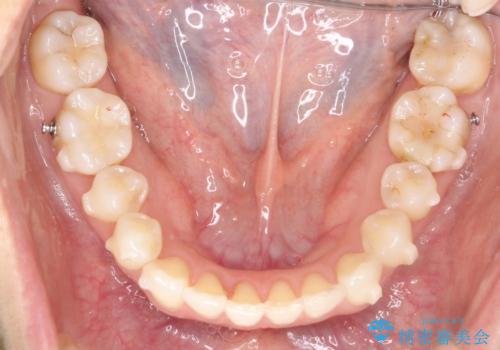

- 矯正装置

- インビザライン

- 治療期間

- 1年5ヶ月

インビザラインで目立たずに治療を終えることができ、喜んでいただけました。